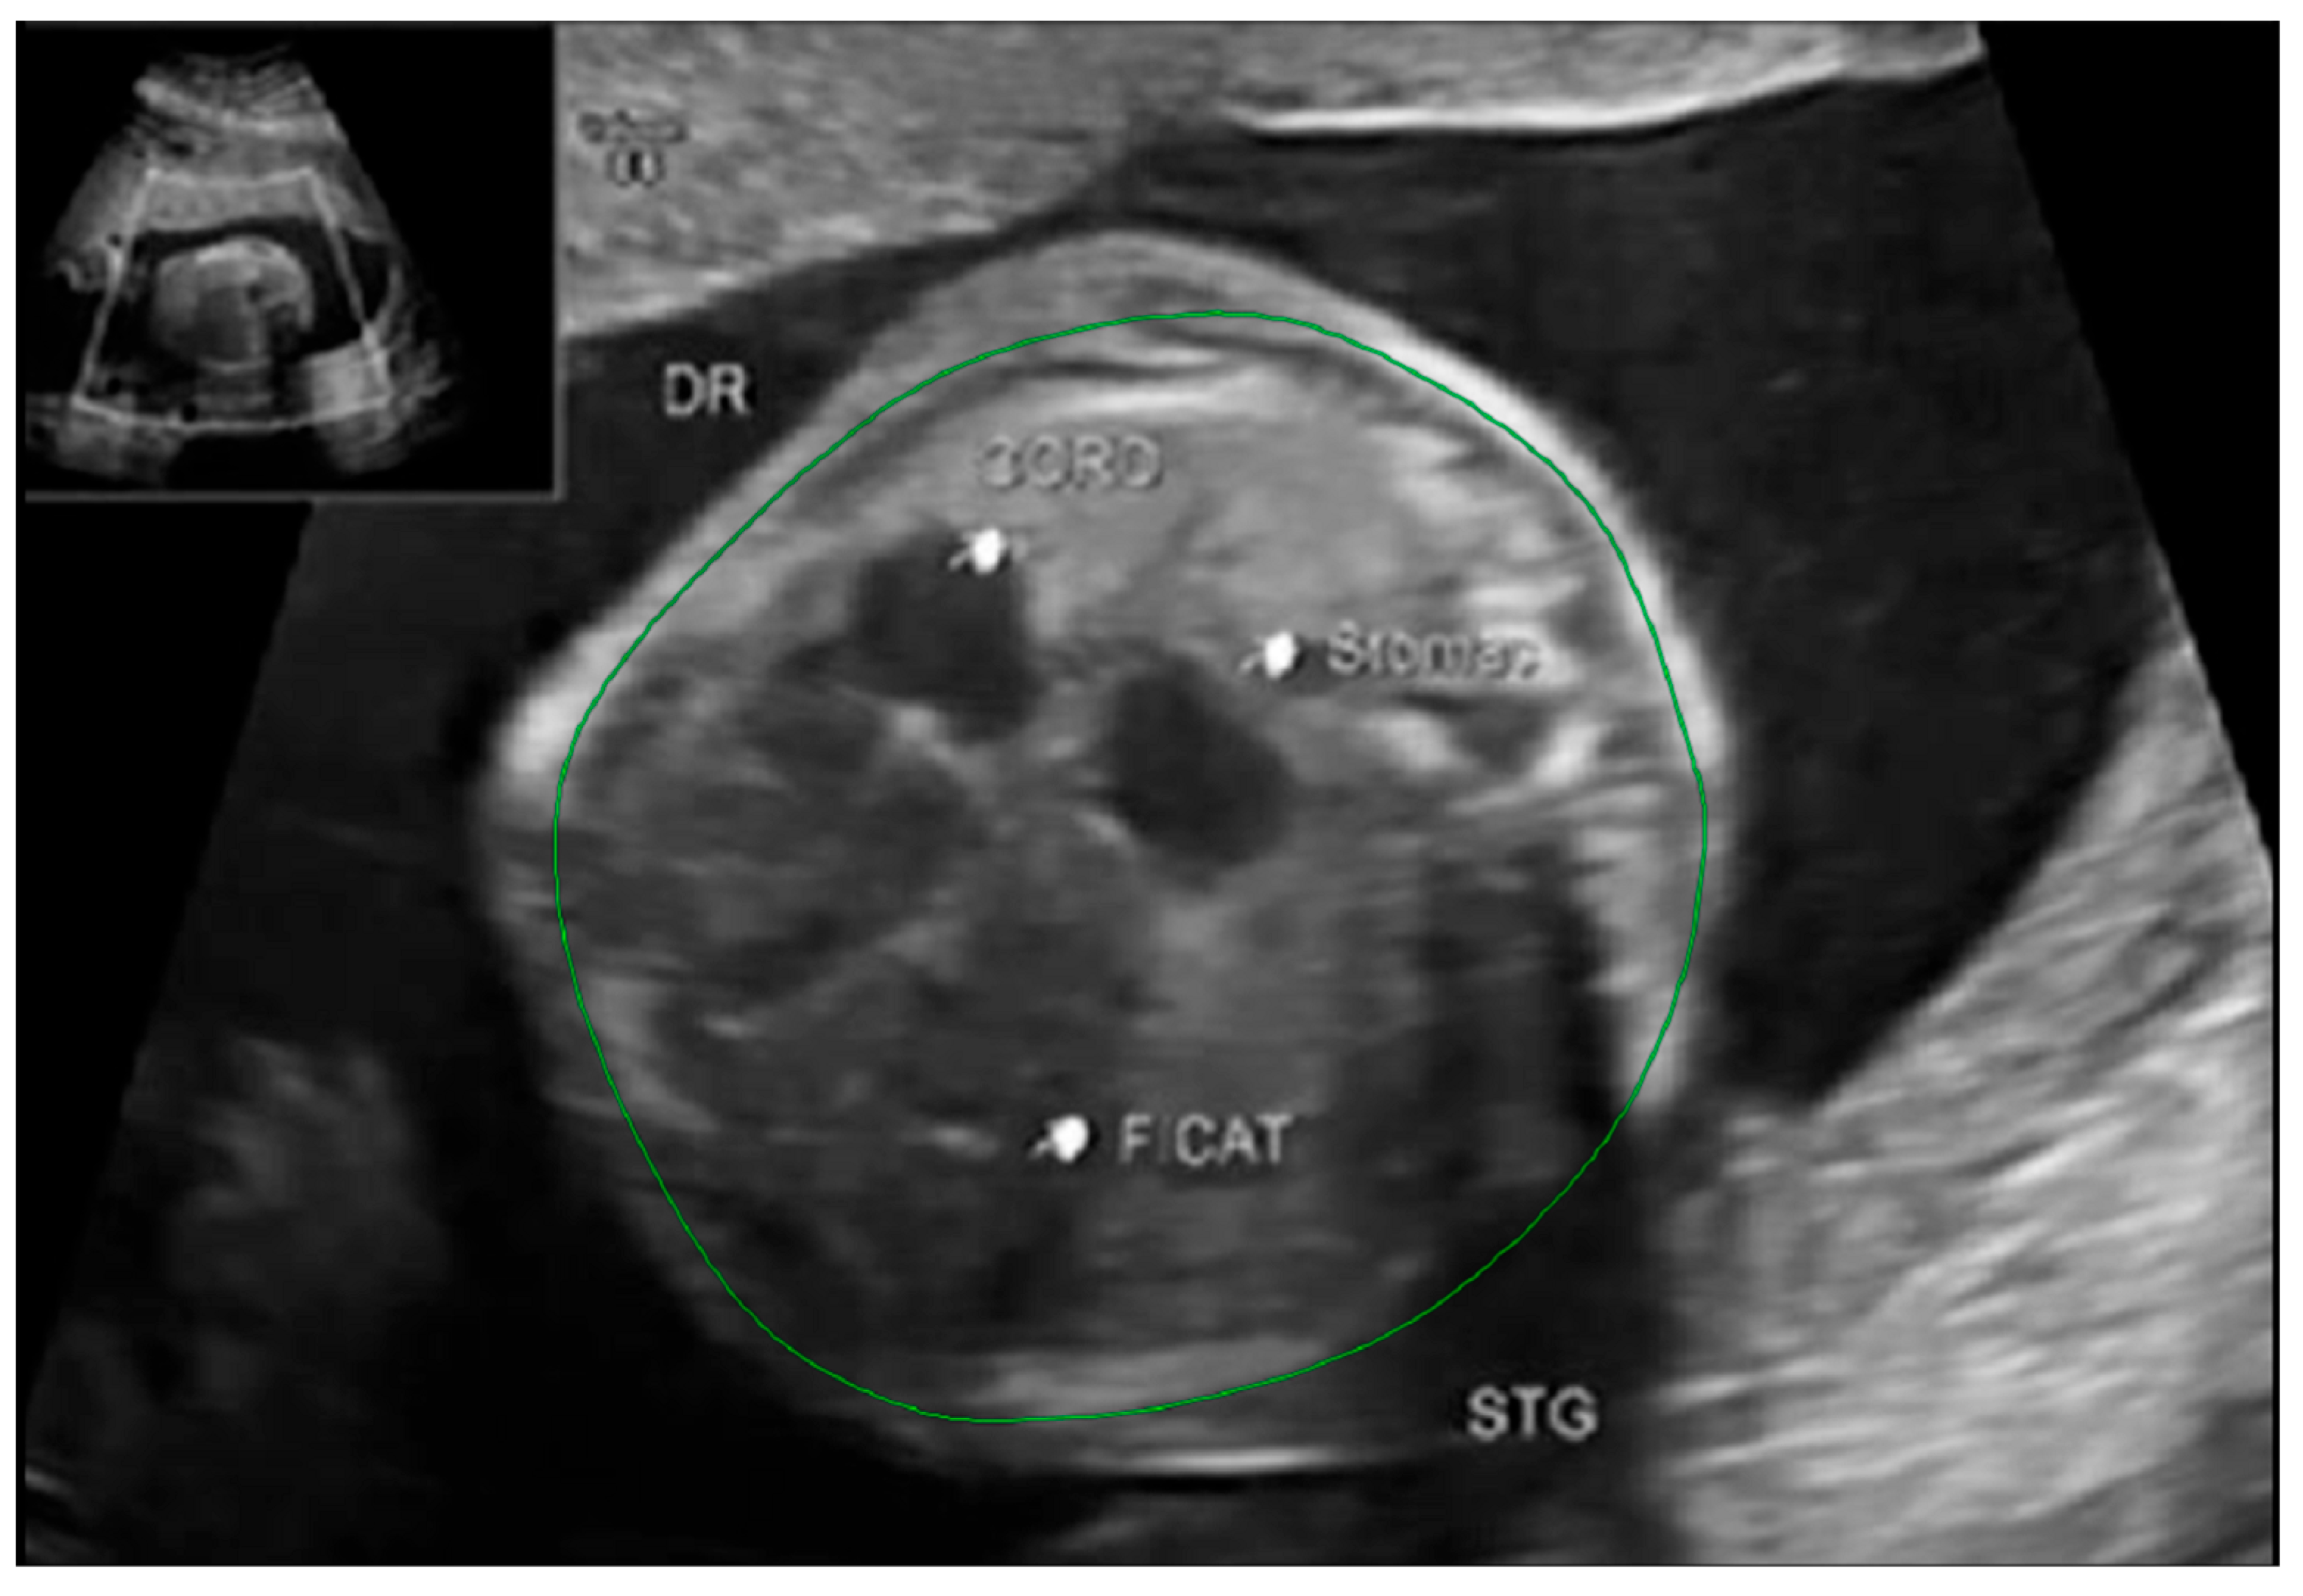

The thoracic circumference was measured following the outer margin of the ribs and respectively tracing the posterior contour of the vertebral transverse and spinous processes. Figure 5 and Figure 6.

Figure 5. MRI axial T2 weighted image of the fetus showing how to measure the thoracic circumference, using the RadiAnt DICOM Viewer program, version number 2022.1.1. The green line represents the thoracic circumference.